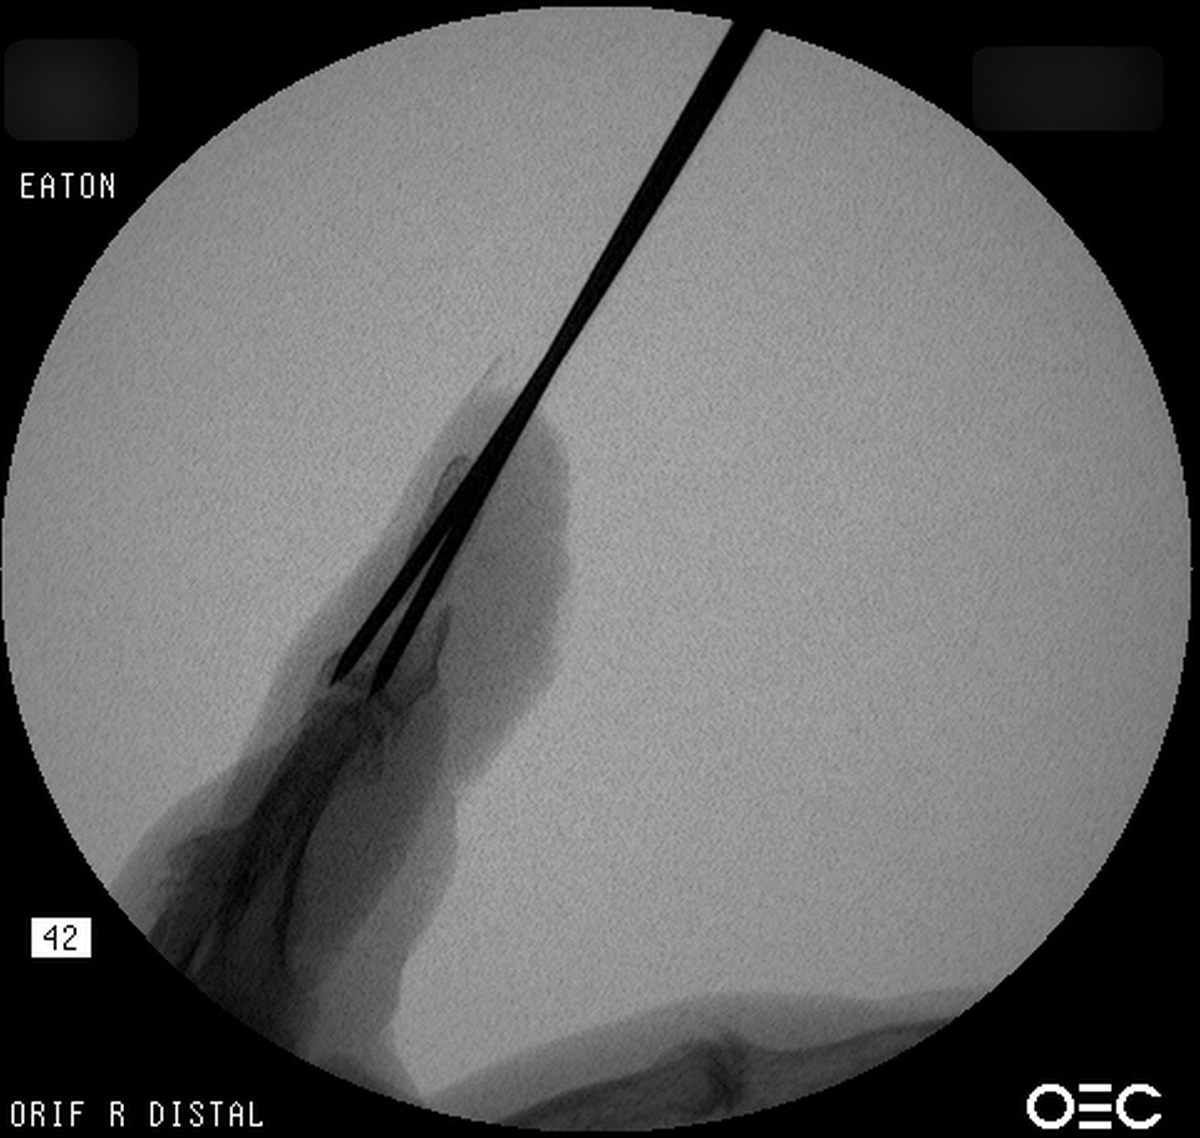

| Case 6 Extraarticular distal radius fracture with angulation and dorsal comminution. |

| Attempts at

closed reduction alone were unsuccessful. |

| Freer elevator

introduced percutaneously as a reduction aid. |

| Percutaneous

fracture stabilization with three pins via the

dorsal radial tubercle, radial styloid and FCR

portals. |